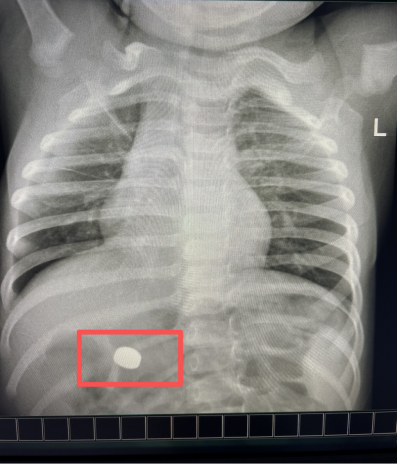

强台风“桦加沙”来袭,风雨交加。一位年仅一岁9个月的幼儿因误吞纽扣电池,被家属紧急送至我院急诊。

纽扣电池是婴幼儿常见的误吞异物之一,其危害不仅在于机械性梗阻,更在于电池在湿润的消化道内会发生泄漏,强碱性液体可快速腐蚀食管黏膜,可能导致灼伤甚至穿孔,处理必须争分夺秒。

消化内科医护人员接到急诊通知后,迅速完成病情评估,当机立断,为患儿开启院内救治绿色通道,确保检查、术前准备等环节一路畅通,最大限度缩短等待时间,同时,紧急联系麻醉科安排急诊手术。